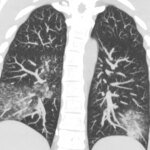

Метапневмовирус человека вызывает волну респираторных инфекций в Китае. Метапневмовирус человека очень похож на Covid или простуду: это не сверхсложное вирусное заболевание, но оно может привести к осложнениям, таким как пневмония.

Метапневмовирус человека из того же семейства, что и респираторно-синцитиальный вирус. Специалисты отмечают, что hMPV вызывает такие симптомы, как кашель, лихорадка, заложенность носа и одышка, которые по продолжительности похожи на симптомы других респираторных инфекций.

Важно понимать, что в более серьезных случаях он может перерасти в бронхит или пневмонию.